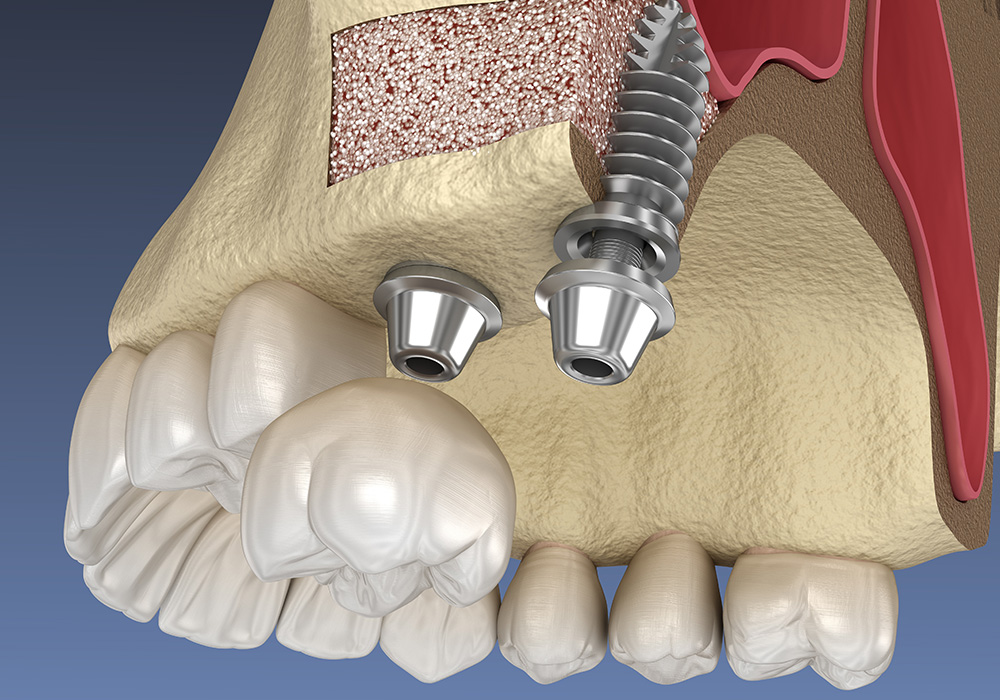

インプラント治療を断られる大きな理由の1つが「顎の骨が少ない」です。どんなにインプラント治療をご希望されても、インプラントを支えるための顎の骨量が少ない場合は、残念ながらインプラント治療を行うことはできません。

しかし、そのような方でも諦めないでください。骨造成や再生療法という治療を行えば、骨を増やすことが可能です。骨の増やし方は、治療箇所や口腔環境によって様々な方法があります。詳しくは、当院の骨造成ページをご覧ください。